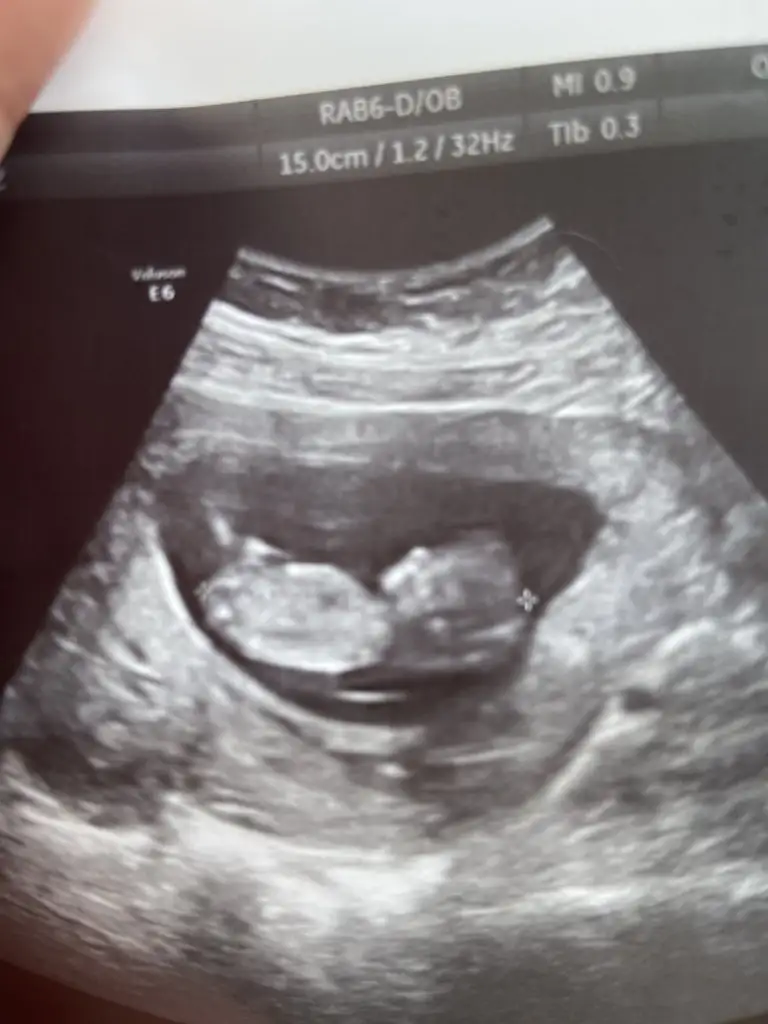

canım kız gibi duruyorBenm bebeğime de tahmin de bulunabilir misiniz. 9+5 haftalik ve usg karindan

Eki Görüntüle 3030308

çok net kız görünüyor canımSelammm , bizimkine de bakar mısınız12 +2 haftalık , karından